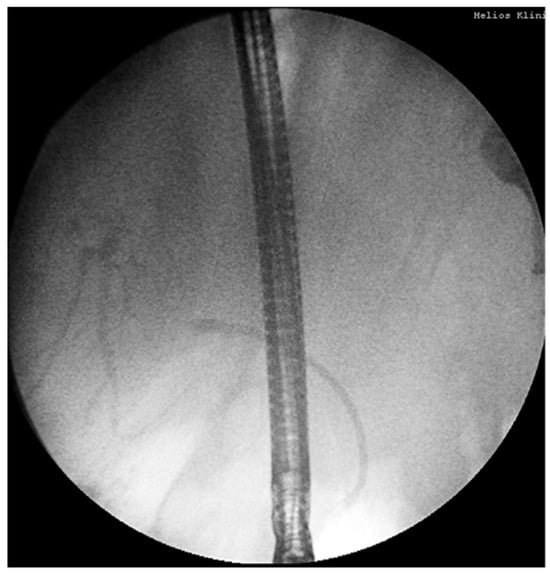

14.02: First ERCP showed normal bile ducts and papilla, no strictures or filling defects (Figure 2).

18.02: Second ERCP again found no obstructive lesion; a 10 Fr/10 cm plastic stent was placed empirically (Figure 4). No clinical or biochemical improvement was observed.

Figure 2. First ERCP (14.02.2025): normal bile ducts, no strictures or filling defects.

Figure 4. Second ERCP (18.02.2025): no obstruction, plastic stent inserted empirically.